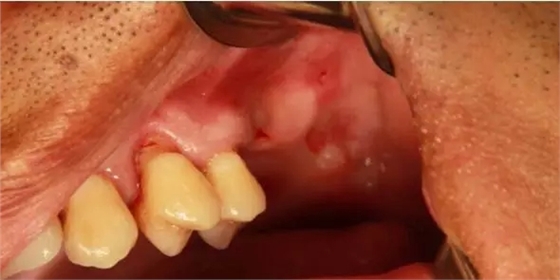

患者50歲,男性,身體健康。左上6,7缺失,骨高度2mm。

術前口內照和CT片。